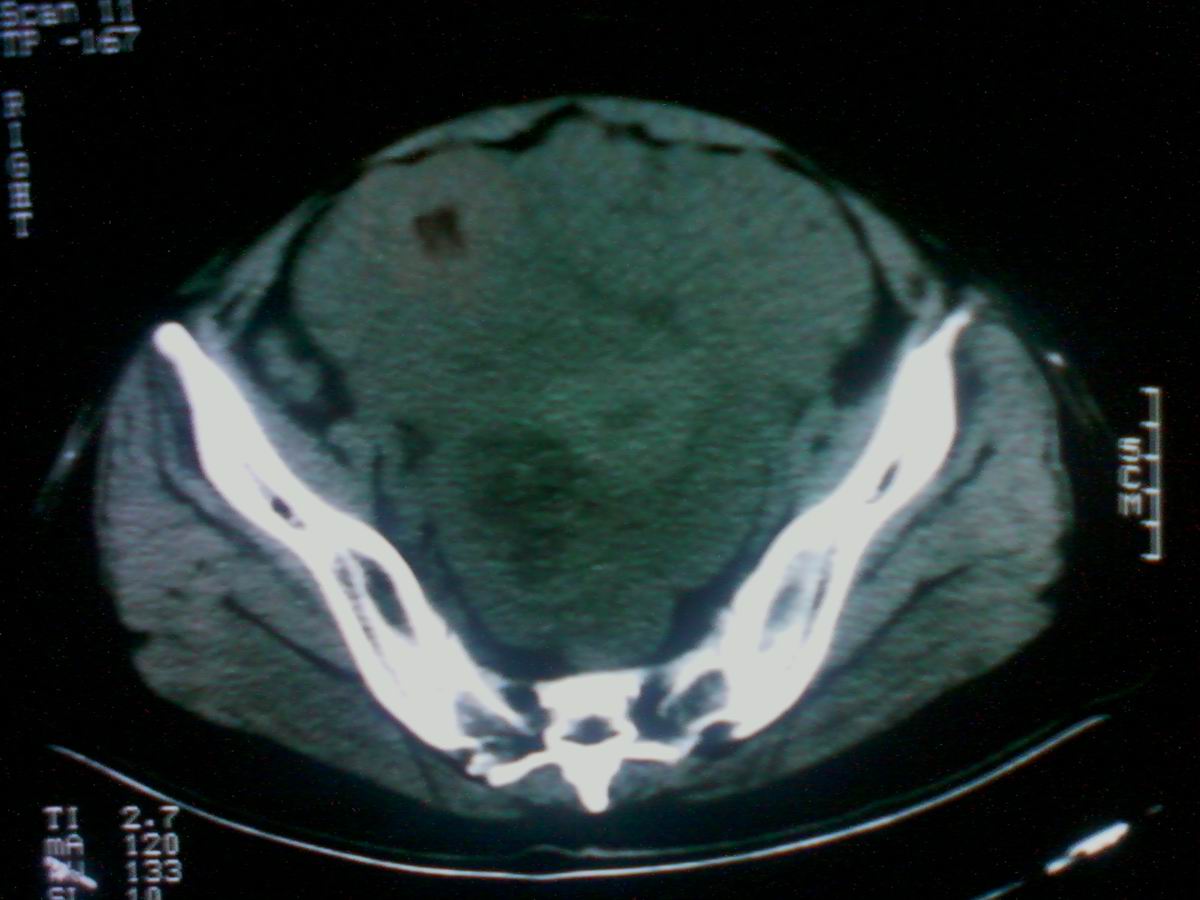

标题: CT25799:女性患者,45岁,腹胀,上腹部疼痛来诊,B超示盆腔 [打印本页]

标题: CT25799:女性患者,45岁,腹胀,上腹部疼痛来诊,B超示盆腔

考虑卵巢癌伴腹水

1)考虑卵巢恶性肿瘤。2)腹水。